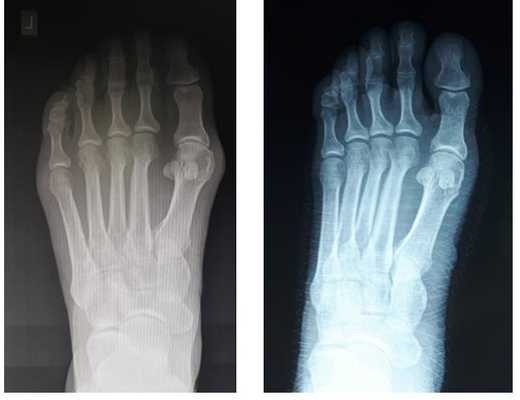

Клинический пример хирургического лечения hallux valgus 2 степени. Пациентка П. 32 лет, обратилась в клинику в связи с прогрессированием деформации 1 пальцев обеих стоп, усилением болей в области 1 плюсне-фаланговых суставов обеих стоп, трудностями с подбором обуви. Вальгусная деформация 1 пальцев или Hallux Valgus является наиболее частой причиной обращения за хирургической помощью к ортопедам, занимающимся проблемами стоп.

При клиническом осмотре обращает на себя внимание наружное отклонение 1 пальцев, расширенный и уплощённый поперечный свод стопы, нарушение плюсневой формулы, гиперкератозы по внутренней и тыльной поверхностям 1 плюсне-фаланговых суставов.

При планировании оперативного пособия выполняются рентгенограммы в прямой и боковой проекции. Производится расчёт углов вальгусного отклонения 1 пальца, угол между 1 и 2 плюсневыми костями, угол артикуляции 1 плюсневой кости. Исходя из рассчитанных углов, выбирается оптимальный метод остеотомии для коррекции имеющейся деформации.